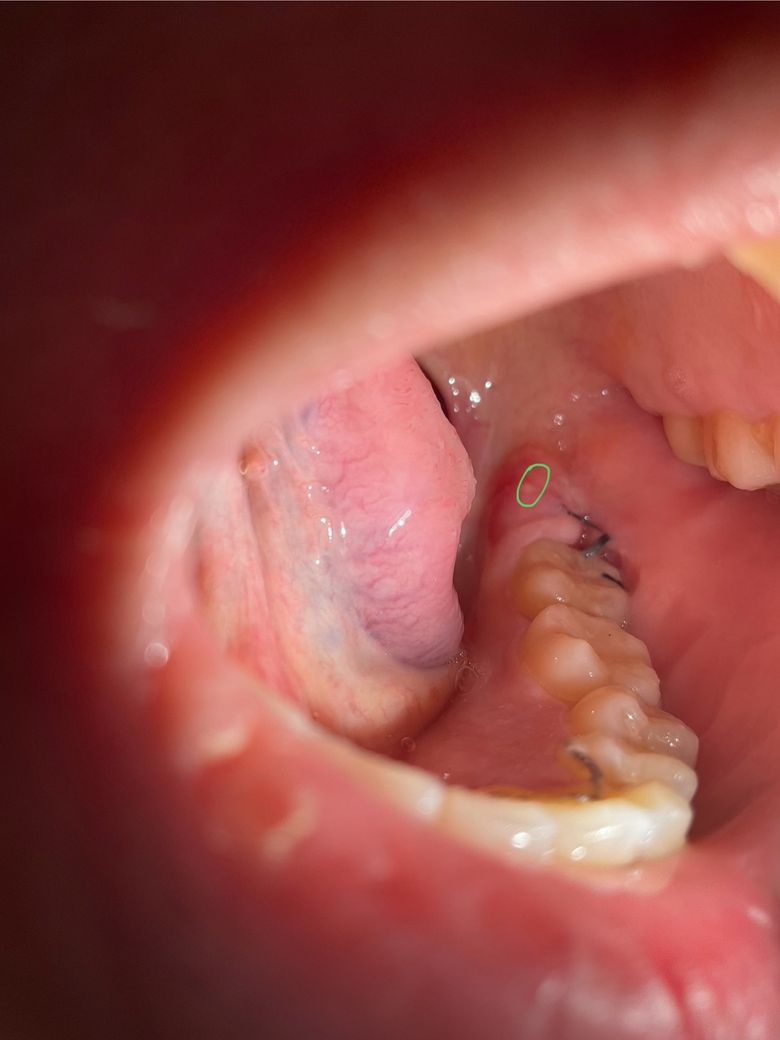

사랑니 발치 후 5일차인데 잘 회복되고 있는 건가요?? 사진 있어요

사랑니 발치 후 5일차 정도 됐습니다

잘 회복되고 있는 건지 궁금합니다!

두번째 사진에서 초록색 표시부위쪽에 하얀 무언가가 있는데 아프지는 않은데 문제가 되려나요??

• 1번 째 사진